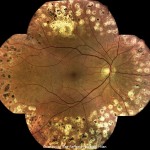

最大80°までの

網膜のパノラマビュー

DRSplusは特別なステッチングアルゴリズムを使用することにより、検者の手を懸けることなく、異なるフィールド画像を自動的に結合します。